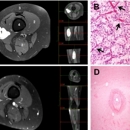

Dosis verlaging Radiotherapie bij myxoid liposarcomen

onder de microscoop uitziet. De pijlen wijzen naar de vele bloedvaatjes die in de tumor te zien zijn. Die vaatjes zijn…